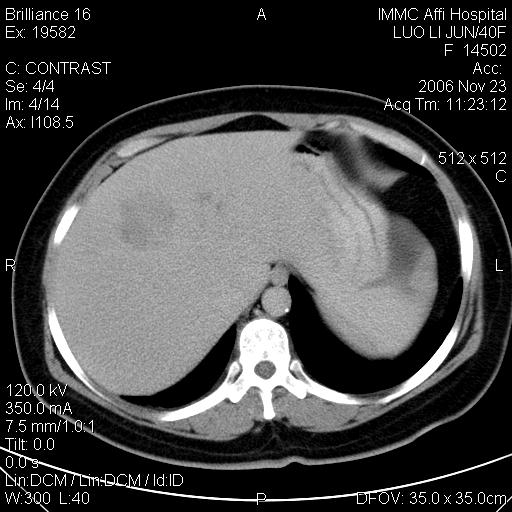

标题: CT5664:我也发一个肝脏的片子大家看看

很典型的肝癌。

速升速降,典型肝癌.

是啊,典型的早出早归!

快进快出典型肝癌.

符合肝癌的增强特征。支持肝癌!

病灶好圆!可能恶性度不高。

不能除外肝细胞腺瘤吧,还是得结合病史。

很好的片子,可惜增强做的比较失败,a期时间没有把我好,实际到了静脉早期了,否则会更典型。

最终考虑是肝腺瘤